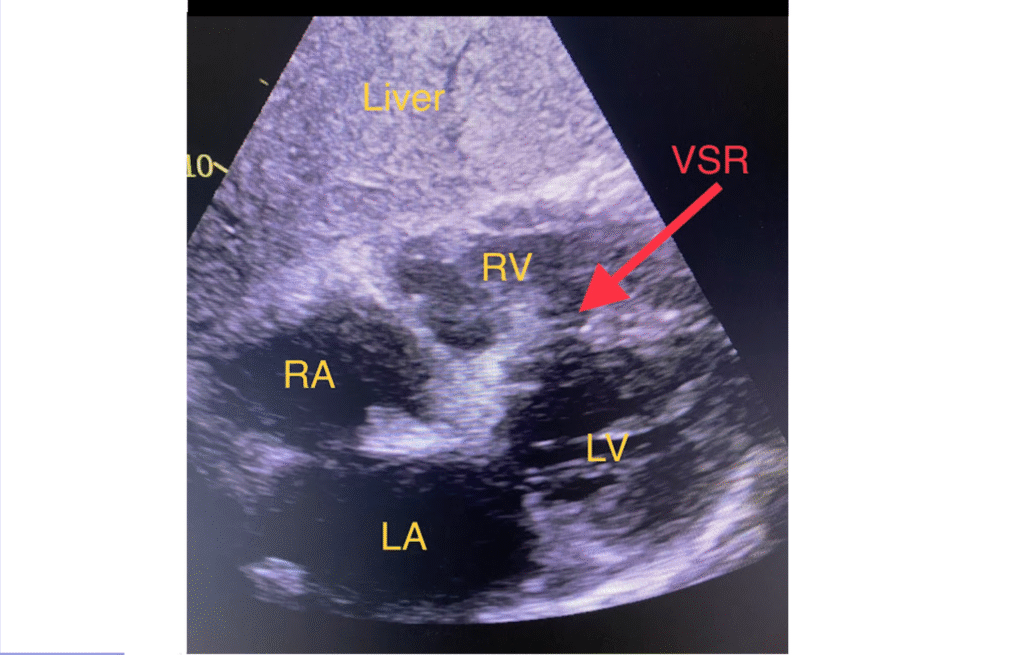

Below is a still image from the above video. The heart chambers are annotated. From the subcostal “window” the heart is viewed through the liver and thus the liver parenchyma is closest to the transducer (top of the image).

- Below the liver is the heart with the right atrium (RA), right ventricle (RV), left atrium (LA) and left ventricle (LV)

- The red arrow points to a large opening in the basal region of the interventricular septum. This is a ventricular septal rupture (VSR).

- As already mentioned, this patient could have post-infarction regional pericarditis from a large completed MI. PIRP is strongly associated with myocardial rupture.

- This patient developed a rupture of the basal portion of the interventricular septum (VSR). The VSR is what is causing the cardiogenic shock!